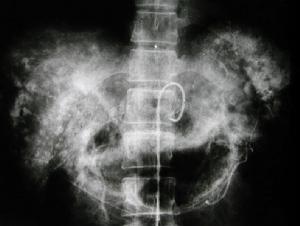

5.肝動脈造影 系一種有創性檢查方法,對血管瘤的敏感性及特異性均高早期注藥後2~3s病灶周邊即有染色造影劑清除緩慢可充盈持續18s以上,造影劑的這種快進慢出的現象是血管瘤的典型特徵,稱之為“早出晚歸征”。

圖1肝海綿狀血管瘤的治療取決於腫瘤的大小部位和生長速度等對於血管瘤直徑小於5cm且無任何臨床症狀又生長於肝實質內者不需特殊處理可門診隨訪B超觀察瘤體的變化如有明顯增大再行手術治療;而直徑大於5cm或有臨床症狀者,因瘤體增大出現對周圍臟器的壓迫症狀和對心血管系統的不利影響或可能出現瘤體破裂危及生命者,則應進行有效的治療。目前對肝血管瘤的治療方法,主要有肝葉切除術、血管瘤綑紮術、肝動脈結紮術,肝動脈栓塞術冷凍治療、微波固化術、瘤體內硬化劑注射術和放射治療等。

1.肝葉切除術 肝葉切除術仍然是目前治療血管瘤最好的方法但因血管瘤血供豐富,術中極易出血,特別是巨大的肝海綿狀血管瘤,由於腫瘤擠壓鄰近臟器局部解剖關係移位,手術難度更大,故應嚴格掌握手術適應證對單發血管瘤尤其是位於肝周邊或病變局限於肝的一側者,可作肝局部切除、肝葉切除或半肝切除術;如病變範圍已超過半肝,余肝明顯代償增大且無肝硬化,肝功能正常者,可作肝三葉切除術。國內一組1120例患者中,行手術切除有683例,其中1例46歲男性患者(圖1)為肝臟特大海綿狀血管瘤,腫瘤體積63cm×48.5cm×40cm占據肝右三葉,行肝右三葉切除術,腫瘤重18kg,術後恢復順利,至今已24年,情況良好可參加正常勞動。對病變已累及第一二肝門或病變廣泛,壓迫鄰近臟器引起症狀者也應儘量將主要病變或壓迫鄰近臟器的肝葉或肝段切除餘下的少量殘瘤可進行血管瘤綑紮術或放射治療。另有1例53歲男性患者,病變位於左外葉及右三葉上段靠近第二肝門,整個左外葉被腫瘤占據,瘤大20cm×10cm×10cm,作了左外葉切除術後殘瘤進行60Co照射50Gy至今已30年情況良好殘瘤未見增大。肝葉切除治療肝血管瘤的主要問題是如何控制術中出血特別是巨大肝血管瘤由於血供豐富瘤體大解剖變位,加上瘤體本身容易出血從而增加了手術難度且可能引起術中難以控制的大出血,所以肝海綿狀血管瘤行肝葉切除術時如何控制出血,是手術成功的關鍵。總結683例手術經驗,肝血管瘤行肝切除中應注意以下幾點:

3.肝動脈結紮和肝動脈栓塞術 對多發性血管瘤或病變範圍極大已侵犯大部分肝組織或緊鄰大血管無法切除者可作肝動脈結紮或栓塞術,根據病變範圍可作肝右肝左或肝固有動脈結紮術結紮後大部分腫瘤可變軟縮小,該法對囊狀血管瘤的療效甚為滿意。在腫瘤縮小的基礎上,術後加用放射治療可促使腫瘤機化變硬對改善症狀、控制腫瘤生長有一定的作用在一組收治的1120例中,有33例行肝動脈結紮或栓塞術,其中1例34歲女性患者其肝上界達右鎖骨中線第4肋間,下界達右肋緣下14cm劍下12cm術中見血管瘤侵犯全肝無法手術切除行肝固有動脈結紮術。術後1個月腫瘤明顯縮小,肝下緣在右肋緣下9cm劍下9cm後經60Co照射60Gy腫瘤繼續縮小隨訪21年肝上界在右鎖骨中線第5肋間下界右肋緣下2cm,劍下3cm,質地變硬患者體重增加肝功能正常已恢復工作。

近年來,隨著介入放射學技術的發展,對已確診為肝海綿狀血管瘤且手術切除可能性較小的患者可經股動脈行肝動脈栓塞術,亦能達到控制血管瘤發展的目的。常用的栓塞劑為碘油、微球(清蛋白微球明膠微球及乙基纖維素微球等)吸收性明膠海綿等,亦可用記憶合金鋼圈行永久性栓塞根據病變範圍可行肝左或肝右動脈栓塞,通常無不良反應,術後大部分患者可見腫瘤縮小。